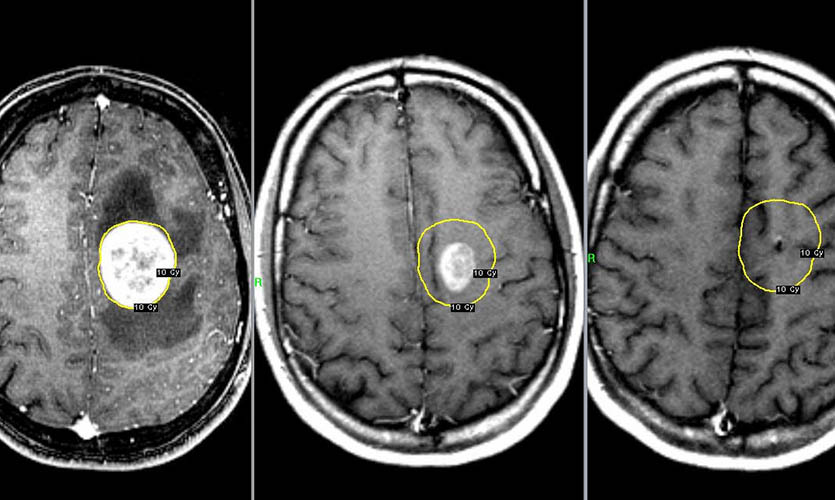

Было проведено исследование радиочастотных электромагнитных полей путём оценки общей кумулятивной дозы удельной энергии (TCSE) для каждого человека. Для каждого случая местоположение опухоли определяли нейрорадиологами, а центр опухоли оценивался компьютерным алгоритмом или непосредственно нейрорадиологом.

Для каждого случая средняя точка опухоли на трехмерной сетке определялась на основе радиологических изображений.

По итогам исследования выяснялось, что у пользователей мобильных телефонов наблюдалось повышение шансов появления злокачественных опухолей головного мозга и развития астроцитомы при использовании мобильных телефонов только с одной стороны головы.

Проще говоря, если ваш смартфон лежит ночью с правой стороны (по статистике именно так), то риск появления опухоли возрастает именно справа.